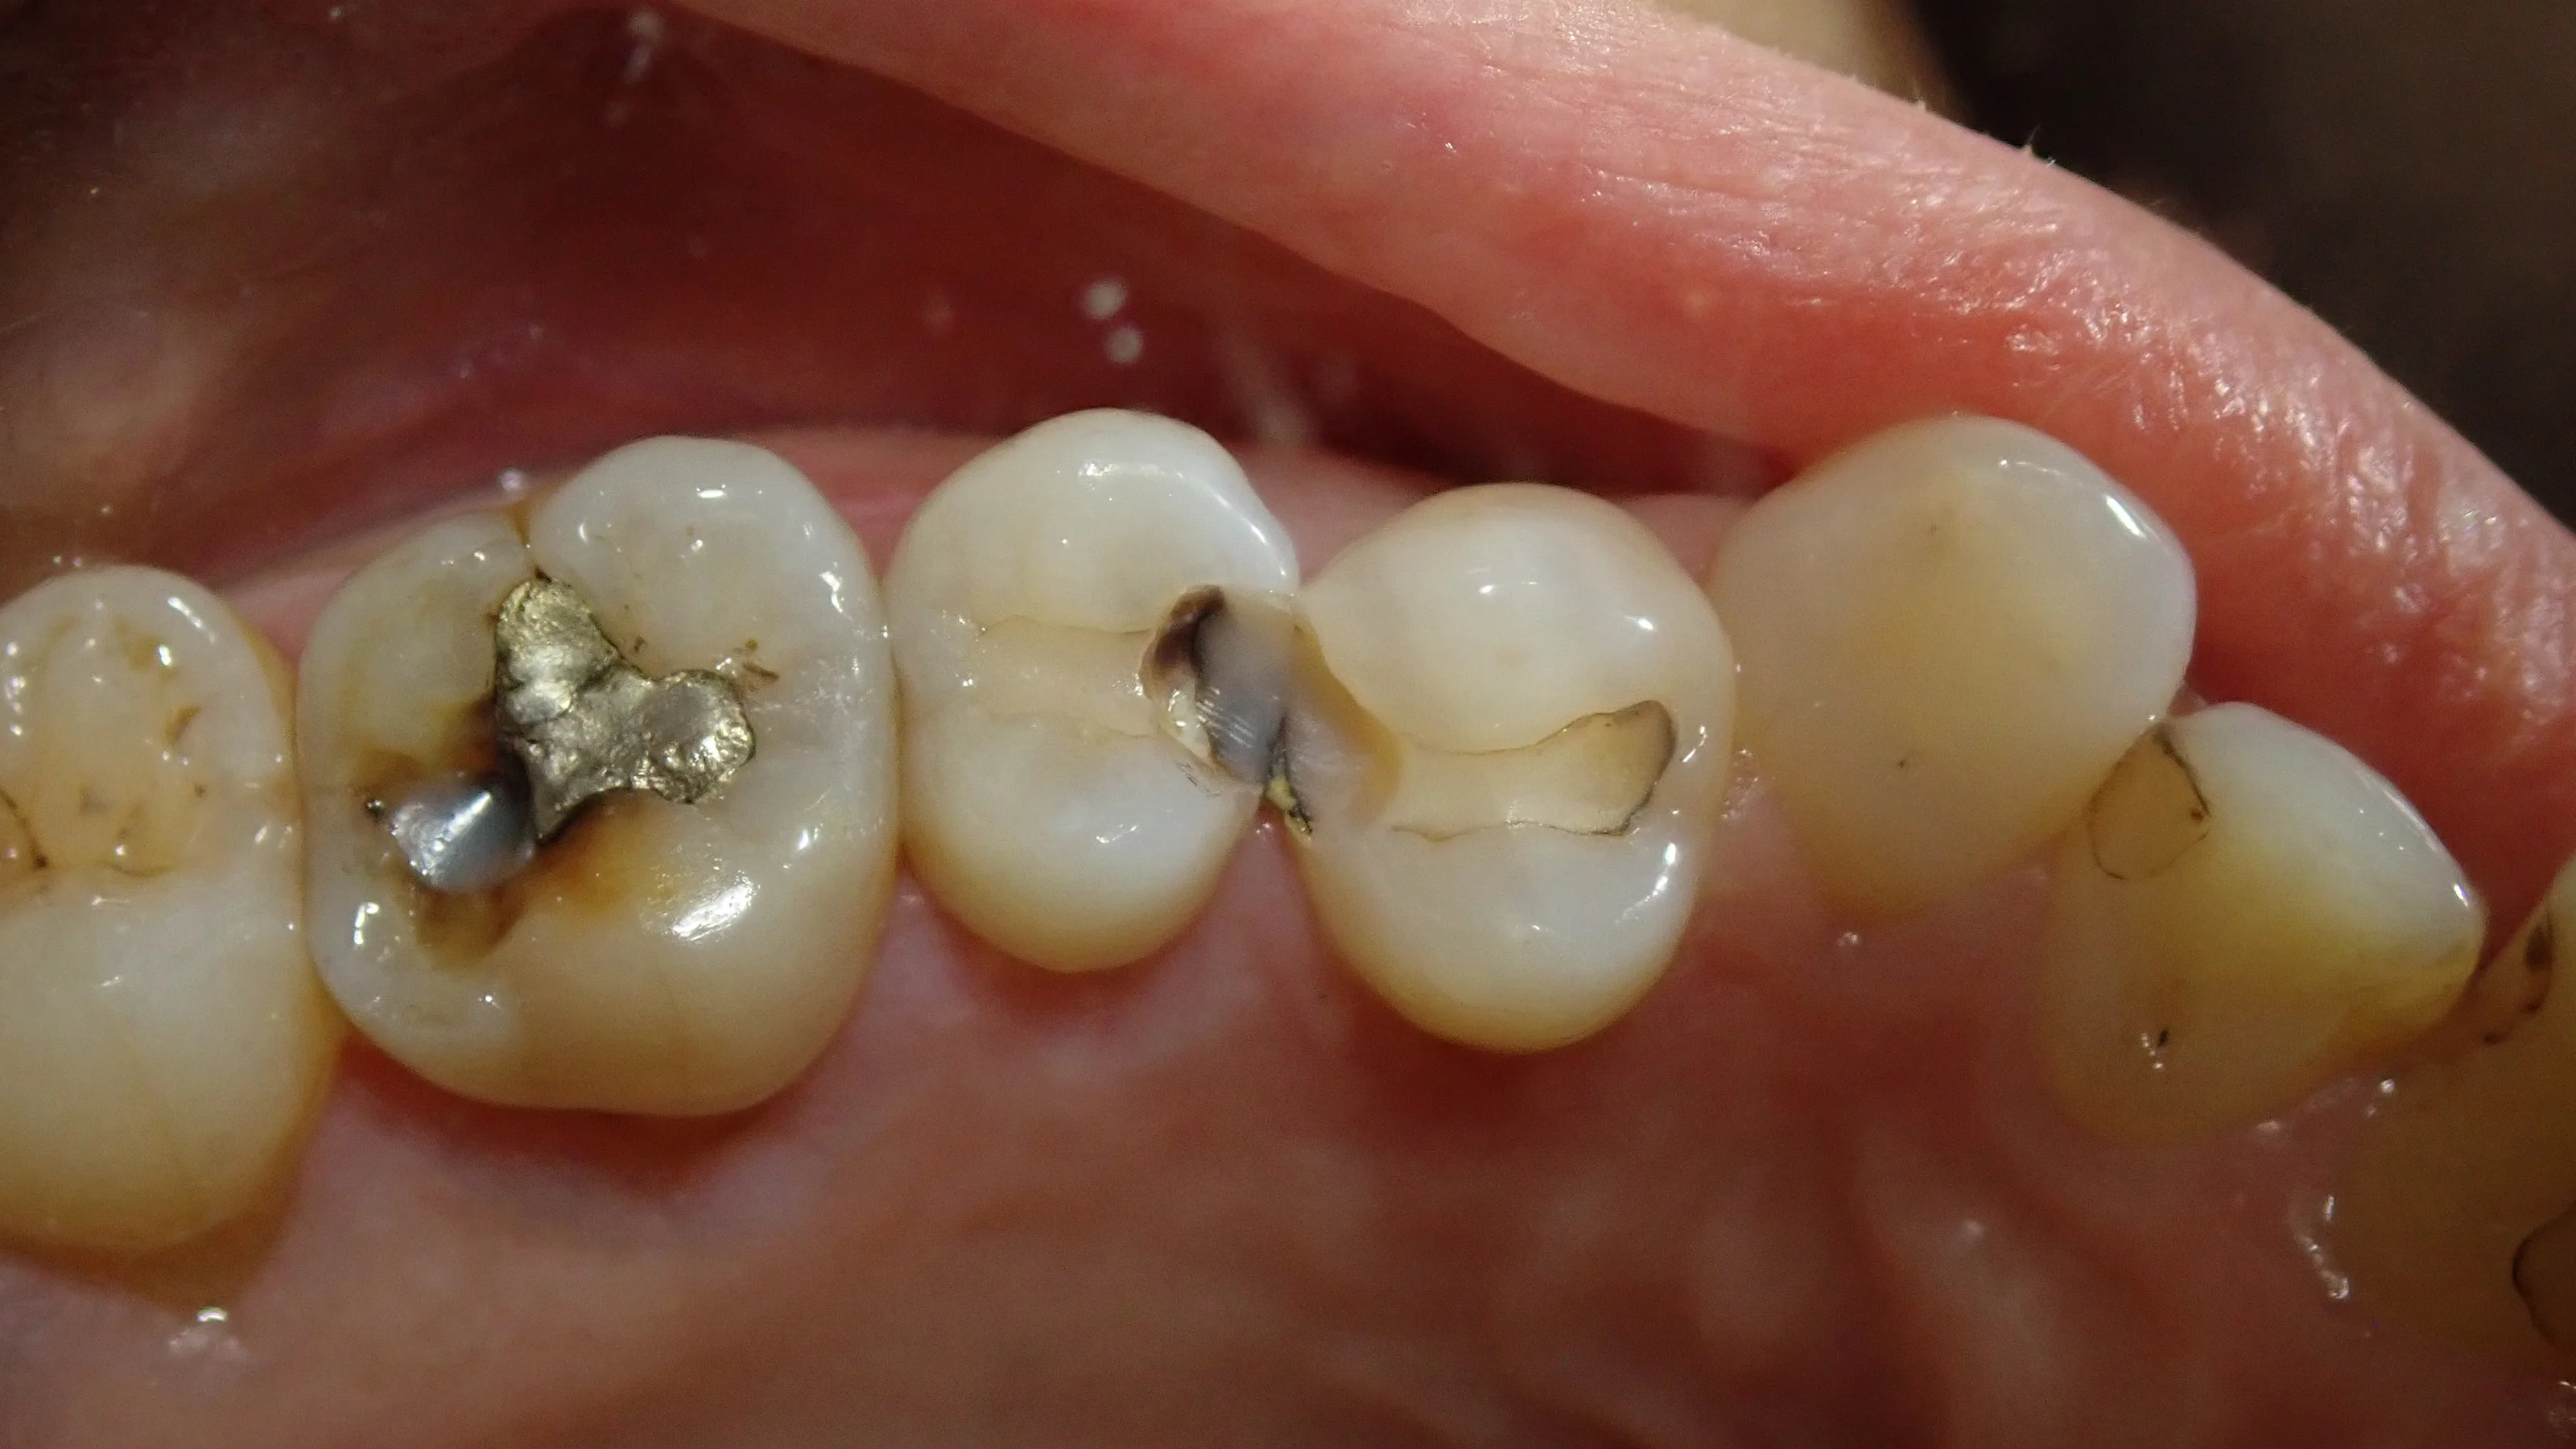

かるーく昔の白い詰め物を削ってみると・・・

割と分かりやすく黒くなっているますね。